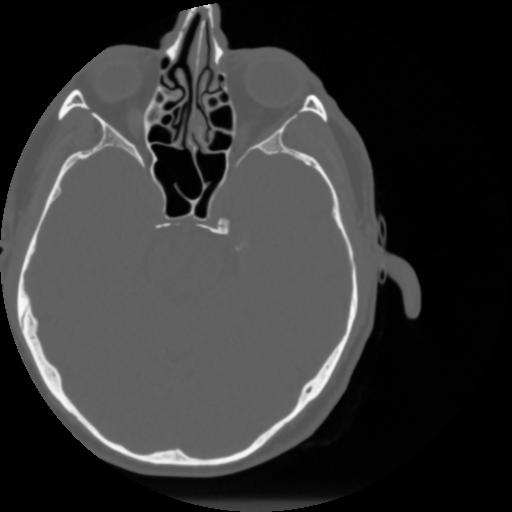

4 CEREBRO,,Vol,0.5,CEREBRO,,